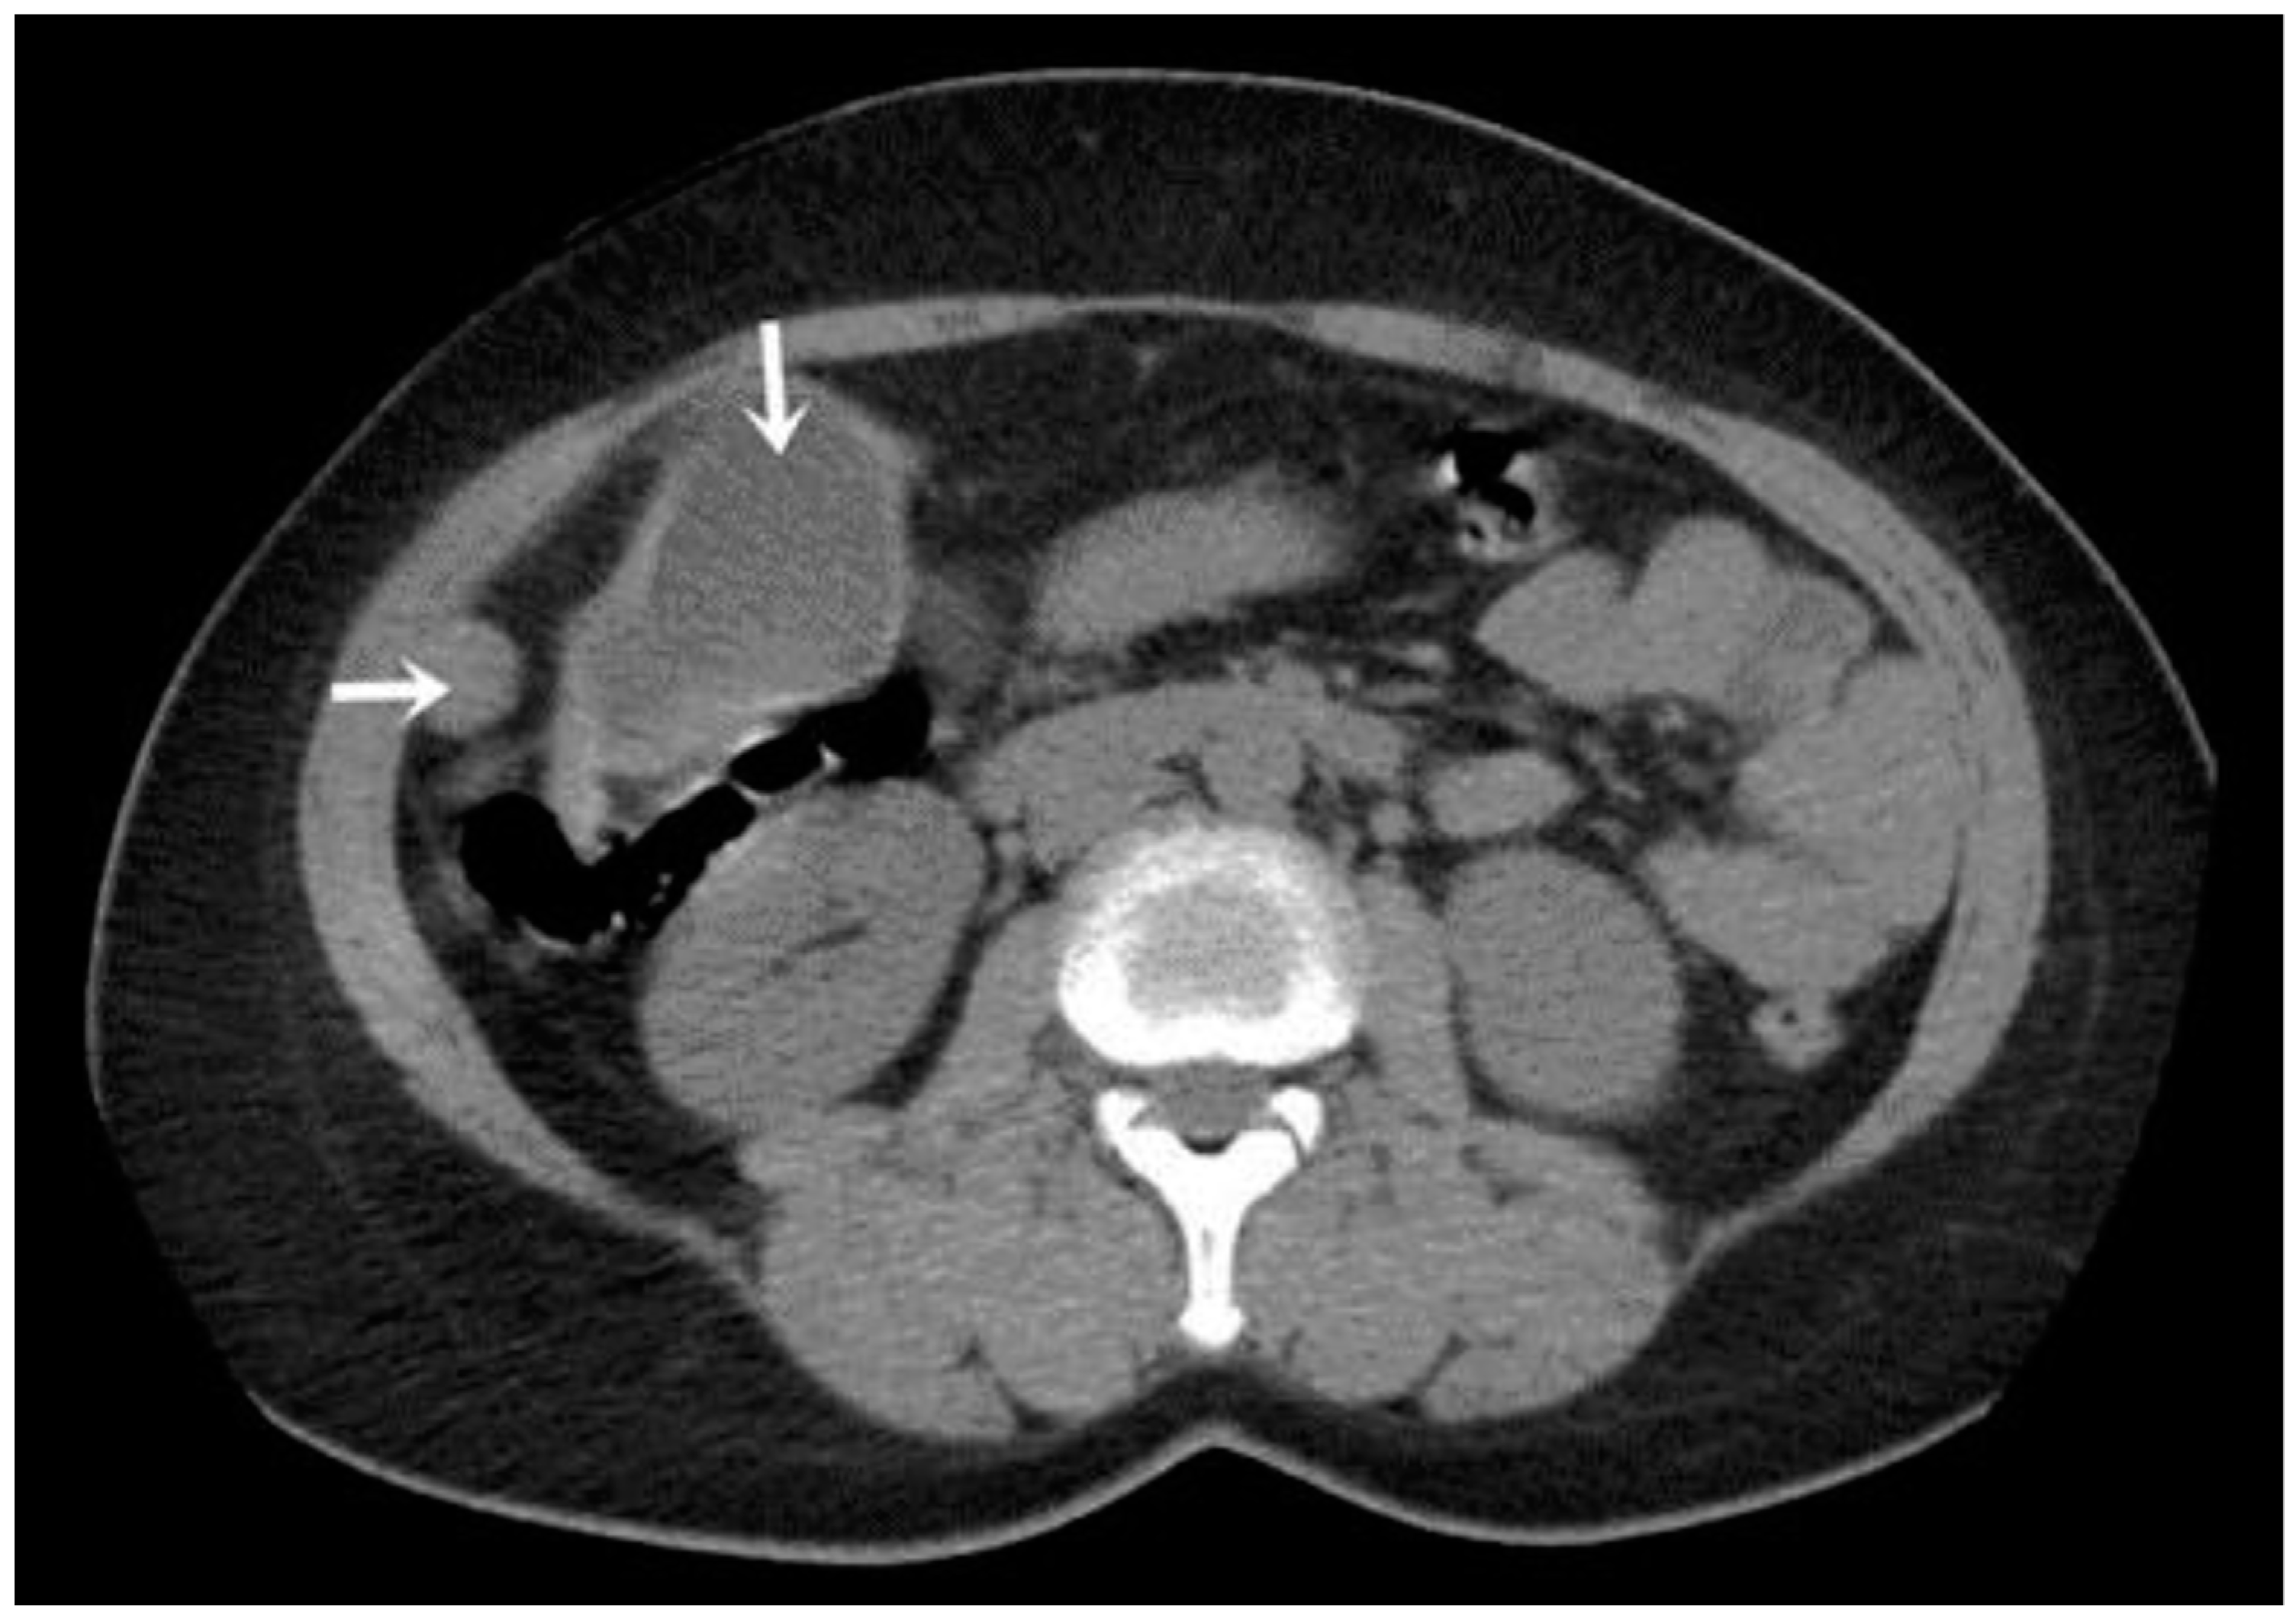

A CT examination revealed multiple cystic images in the hepatic segments V, VI, and VII, with subhepatic extension and involvement at the fissures of the venous ligament. Cystic images were also observed in the anterior abdominal wall and submesocolic (Figure 5, Figure 6, Figure 7, Figure 8 and Figure 9). Blood tests showed no significant abnormalities, and ELISA determination of IgG class antibodies to Echinococcus granulosus was positive at 1.66 IV (with values considered negative at ≤0.9 IV and positive at ≥1.1 IV).

The imaging highlights hepatic cysts in segments V, VI, and VII, a large cystic formation in the round ligament, a cyst in the parietal peritoneum, two cysts in the greater omentum, and two cysts located in the submesocolic enteral mesentery.

Figure 6. Mesenteric hydatid cyst (indicated by arrow).

Figure 8. Peritoneal (black arrow) and round ligament cysts (white arrow).